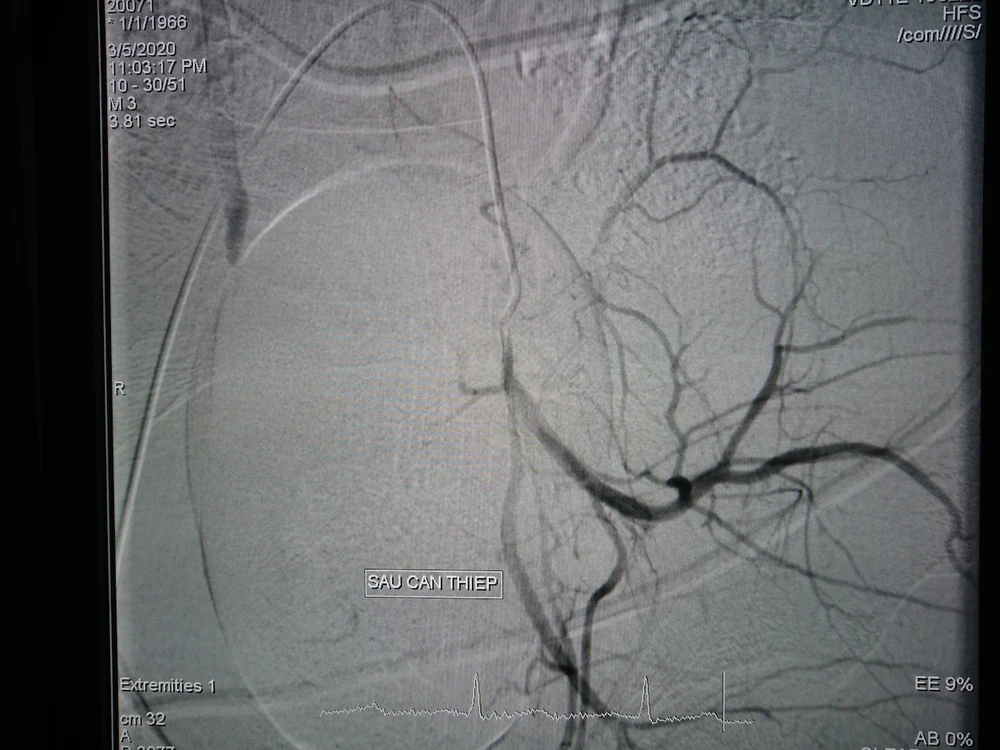

Hình ảnh trước và sau can thiệp nút mạch 1 Hình ảnh trước và sau can thiệp nút mạch 2

Hình ảnh trước và sau can thiệp nút mạch.

Êkíp can thiệp mạch do BS CK1 Trần Công Khánh - Phó Trưởng khoa Chẩn đoán hình ảnh đã tiến hành chụp và phát hiện nhiều ổ thoát mạch xuất phát từ động mạch bàng quang. Êkíp luồn chọn lọc vào động mạch bàng quang, chụp xác định vị trí và bơm tắc bằng Spongel. Chụp ảnh kiểm tra sau bơm tắc không thấy tắc mạch.